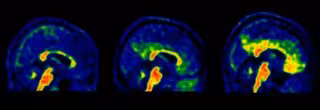

Diversos investigadors del Barcelona Beta Brain Research Center (BBRC), el centre d'investigació de la Fundació Pasqual Maragall, han identificat nous valors de referncia d'un biomarcador associat a l'Alzheimer, que permetran ampliar el nombre de persones candidates a les estratgies de prevenció.

Concretament, els investigadors han establert un nou llindar més baix a partir del qual es comena a acumular en el servei de manera patolgica la protena beta amiloide, una de les alteracions biolgiques que es produeixen al cervell amb Alzheimer, segons un comunicat d'aquest dimarts.